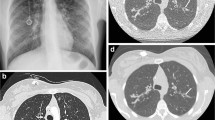

The basis for each score is the morphological, pathological alteration of the lung. These appear with different emphasis depending on the imaging modality: bronchial wall thickening, bronchiectasis, consolidations, bullae, mucus plugs and hyperinflation (Figs. 1, 2, 3, 4, 5 and 6) [16, 17]. In addition, functional assessment of regional changes in ventilation and perfusion is also desirable as complementary information.

Magnetic resonance images in a 16-year-old girl with bronchiectasis in the upper lobes (arrows). a Coronal respiratory-triggered T2 fast spin echo and self-gated ultra-short echo time sequences with (b) coronal, (c) axial and (d) sagittal multiplanar reconstructions. Please note that air trapping distal to the dilated bronchi is only depicted in the latter